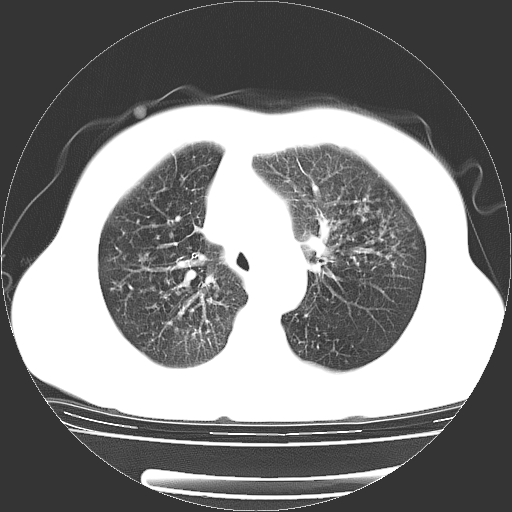

标题: CT23067:女,70岁,咳嗽、咳痰一个月,低热一周。 [打印本页]

女,70岁,咳嗽、咳痰一个月,低热一周。

1.左上肺结核,部分纤维化。右肺中下叶部分肺不张,内见液化、坏死及点状钙化,右中下叶支气管壁增厚、管腔狭窄,见多个点状钙化,结合临床考虑支气管内膜结核,建议痰检查抗酸杆菌并参考血沉。两肺多个小圆点状高密度灶,境界模糊,多考虑结核肺内播散。但本人年龄较大首先应支气管镜检以除外右肺癌。